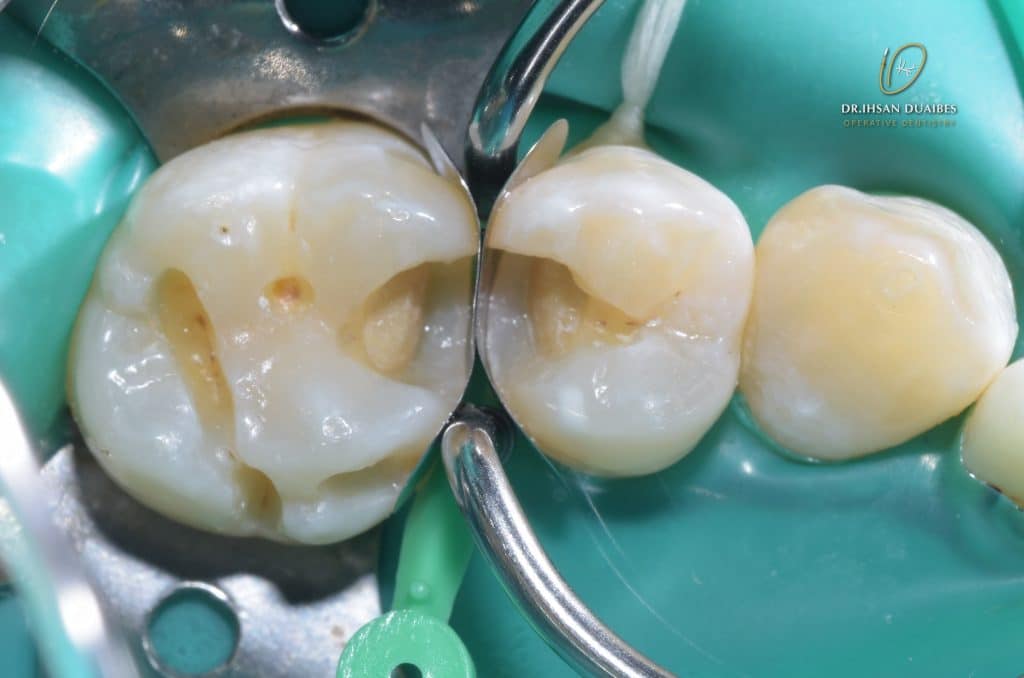

After initial observation ( GIC reduction )

Choosing correct wedge and matrix stripes

Matrix

Building proximal walls ,then Remove the matrix ( Remove matrix stripes with mosquitto )

Dentine layer A3.5